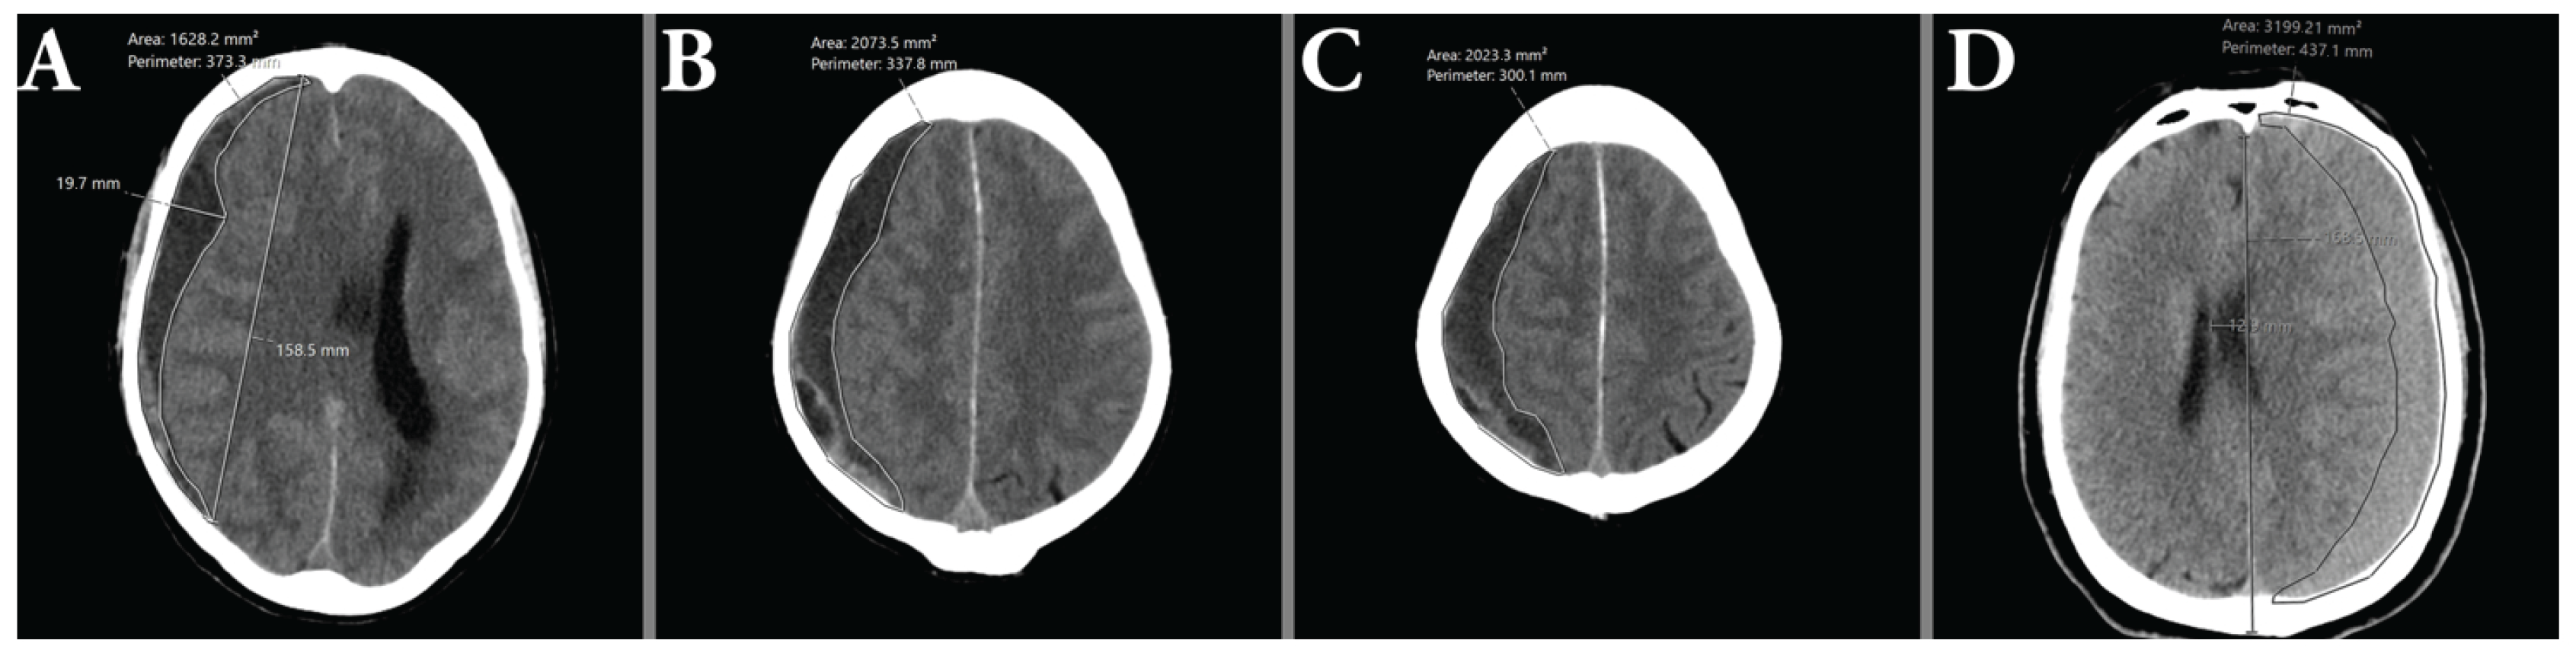

2.7. Hematoma Volumetry

2.8. Hematoma Characterization

2.9. Uni- and Bilateral Hematomas